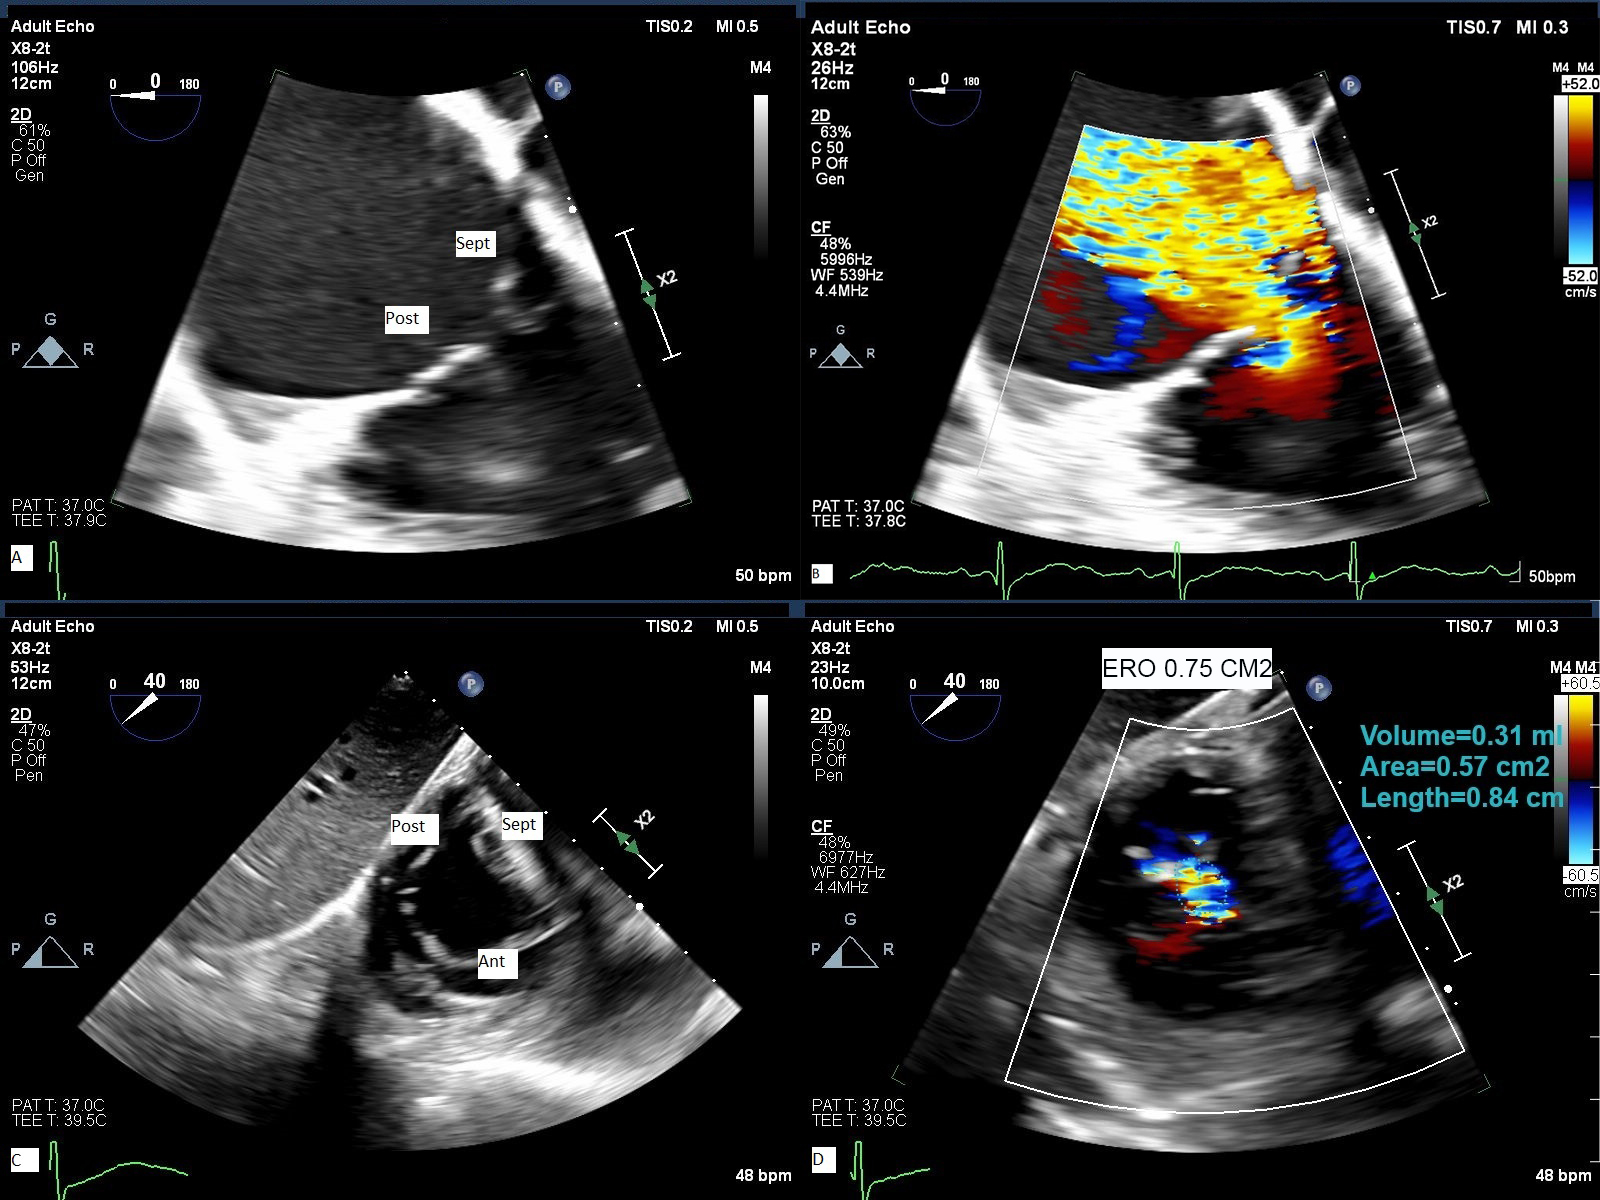

Fig. 4.

TEE assessment of TR. 2-D TEE from deep esophageal view (A) with color flow Doppler (B) and from trans- gastric orthogonal plane view (C) with color flow Doppler (D) demonstrate severe to massive TR. Ant, anterior leaflet; Post, posterior leaflet; Sep, septal leaflet; ERO, effective regurgitant orifice area obtained by planimetry of non-coaptation area delimited by color flow Doppler.

Three-dimensional Echocardiography (3-D echo) has been an important addition to imaging tricuspid valve and like for mitral valve, it obviates the need for mental reconstruction and identification of leaflets. However, the quality of 3-D echo images depends significantly on the quality of 2-D echo and since tricuspid valve is an anterior structure 3-D TTE images may sometimes have better quality than 3-D TEE images. In addition, 3-D echo systems have lower resolution than 2-D echo and higher far field attenuation which may cause 3-D imaging more challenging to acquire. At our institution, we acquire 2-D and 3-D TEE images from mid esophagus and deep esophagus position as well as trans-gastric position with clockwise rotation (Figs. 4,5). The trans-gastric view is very important for pre-procedural identification of leaflets morphology and measurement of non-coaptation area. We measure the vena contracta in orthogonal plane at mid esophageal view and effective regurgitant orifice area (EROA) from short axis trans-gastric view. The flow convergence radius is measured after reducing the Nyquist limit to ~28 cm/sec. Having part of adjacent anatomic structures such as coronary sinus and aortic valve in the acquisition field may improve the image orientation and identification of different leaflets (Supplementary Videos 7–11). There is a learning curve in imaging tricuspid valve and determining the degree of TR by 2-D and 3-D TEE. The American Society of Echocardiography (ASE) guidelines recommend orienting the aortic valve on the left of the frame and interatrial septum in the far field at 6 o’clock when looking at the valve from RV or RA view [33].